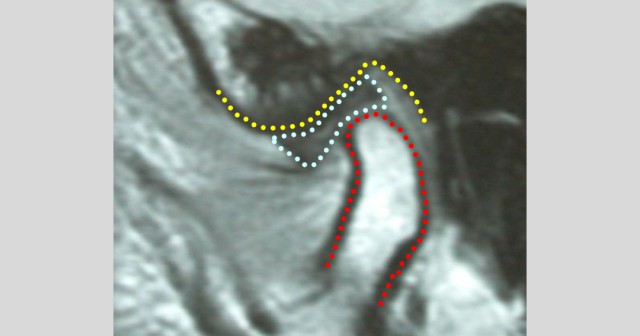

Centric relation involves patients whose condyle-disc assembly involves “normal joints fitting into normal sockets.” But often, that’s not the case.